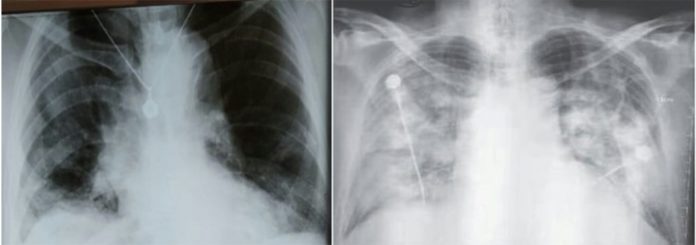

Mjeku Tritan Kalo ka publikuar mbrëmjen e sotme imazhet radiologjike të mushkërive të dërmuara nga koronavirusi të një pacienti të infektuar, ndërsa bën thirrje për vetëizolimin e qytetarëve.

VETËIZOLOHUNI…VETNDËRGJEGJËSOHUNI….PËRKUJDESUNI për veten tuaj….Në këto ditë të “luftës me Covid-19”, unë si mjek, si qytetar, si prind e si Shqiptar, në mes fotove të mëposhtëme: 1- të udhëve të zbrazura, 2- të tre MANTELBARDHËVE në një pushim të shkurtër të kësaj beteje, dhe 3- të imazheve radiologjike të mushkërive të “dërmuara nga agresori tinzar e jetëmarrës” Sars-Cov-2, do të preferoja për të gjithë JU bashkëkombasit e mi, vetëm atë të parën….